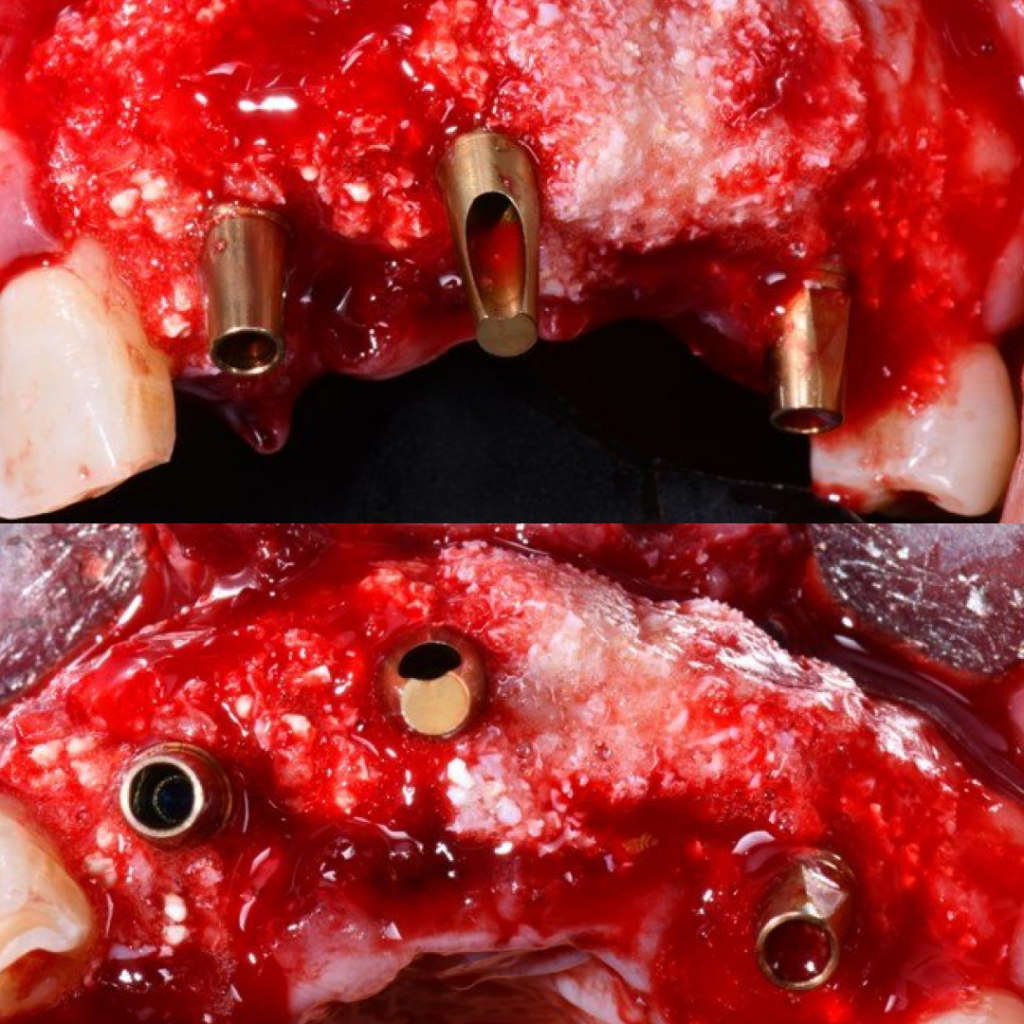

- Заполнение костных дефектов смесью из костного материала TI-oss, аутокости пациента и обогащенной тромбоцитами плазмой PRP

Благодаря уникальному дизайну имплантатов AnyRidge становится возможным получить блестящую первичную стабильность даже при наличии объемных костных дефектов, что позволяет в большинстве случае дать немедленную нагрузку на имплантаты и зафиксировать временный мостовидный протез

в эстетически значимой зоне в день операции.